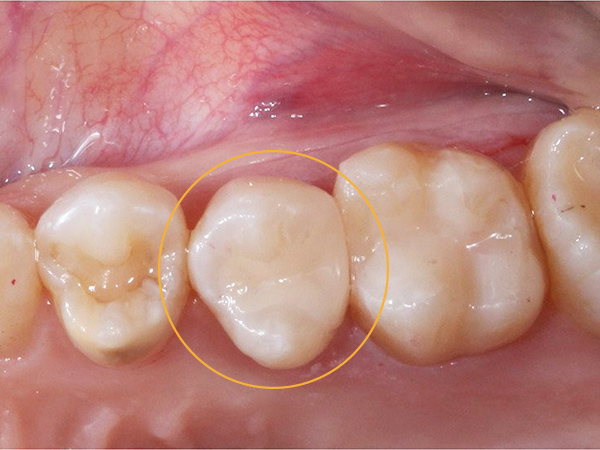

症例

治療前後写真

治療前

治療後